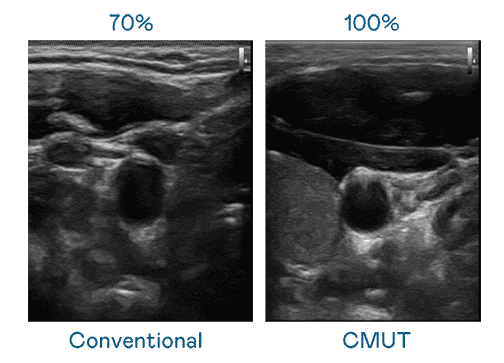

CMUT 技术是一种用电容式微机电元件来产生超音波讯号的技术。。与传统 PZT 压电式技术相比,,,CMUT 频宽增加 30%,,,更宽频的超音波讯号让影像解析度大幅提升,,,,是实现高影像品质医疗超音波扫描、、、促进精准医疗发展的关键技术。。。

大频宽带来超清晰影像

超音波影像的解析度高低,,,首先取决于探头能发出的讯号频宽。。。。william威廉中文官网 CMUT 可提供高清晰的超音波讯号,,,提供高频宽、、高灵敏度、、、影像纹理细节更高的超音波影像,,,,协助医护人员缩短影像判读时间及利用精准的医疗影像进行诊断。。。